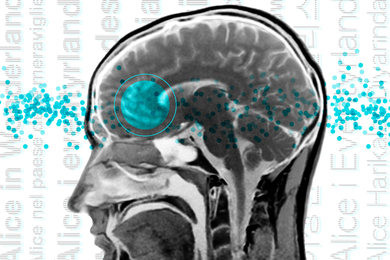

Prof. Evelina Fedorenko speaks with Atlantic reporter Matteo Wong about her research exploring how “the brain behaves when an individual speaks different languages.” Fedorenko explains that “it seems like languages provide us with mappings between forms and meanings.”